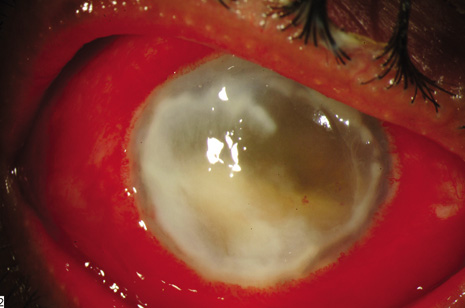

CONJUNCTIVAL FILTERING BLEB-ASSOCIATED ENDOPHTHALMITIS

This category of endophthalmitis is similar to acute postoperative endophthalmitis in that these patients manifest a sudden onset of pain, visual loss, conjunctival congestion, purulent bleb involvement, and the typical diagnostic features of acute-onset endophthalmitis (Fig. 8).10,11,104 Risk factors for this category of endophthalmitis include a history of conjunctivitis, contaminated topical glaucoma medications, the use of contact lenses, and inferior filtering bleb.10,104 The incidence of bleb-related endophthalmitis after a glaucoma-filtration procedure with mitomycin C may be higher than for trabeculectomy without antifibrotic agents.104 The organisms frequently involved in this type of endophthalmitis include streptococcal species8,71 and Hemophilus influenzae. Because of the frequency of these virulent organisms and the generally poor visual acuity outcomes, PPV and intraocular antibiotics are often considered as the initial approach for conjunctival filtering bleb-associated endophthalmitis.

Fig. 8. Delayed-onset endophthalmitis associated with glaucoma filtering blebs. Organisms invade the bleb initially and spread to involve intraocular fluids and tissues. This patient shows characteristic purulence of the filtering bleb, conjunctival congestion, hypopyon and fibrin in the pupil. Streptococcus pneumoniae was isolated from the vitreous specimen.